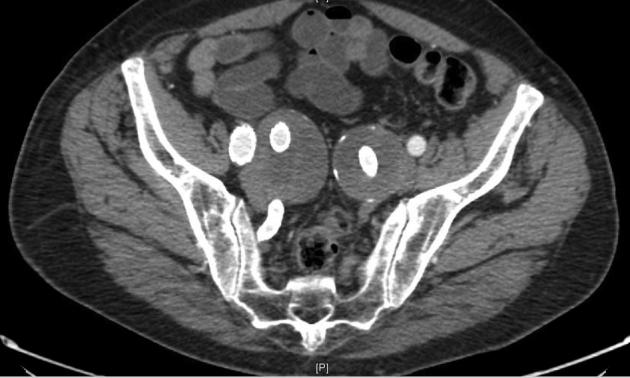

Bilateral GORE Iliac Branch Endoprosthesis with prior open abdominal aortic aneurysm repair.

The GORE Iliac Branch Endoprosthesis (W. L. Gore & Associates, Flagstaff, Ariz) has been approved by the Food and Drug Administration for use in the treatment of aortoiliac and common iliac aneurysms, with promising results to date. The efficacy of using the device to overlap with a Dacron graft has yet to be elucidated. We present the case of a patient with prior open abdominal aortic aneurysm repair who we treated with bilateral iliac branch endoprostheses.